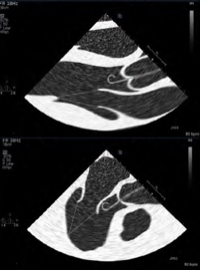

🧐¿Qué le pasa a mi Impella?⁉️

🔴Curva marcada: presión "ventricular "

🟢PLANO😱: MISMA CAVIDAD (ventrículo! "colado") ImageImage